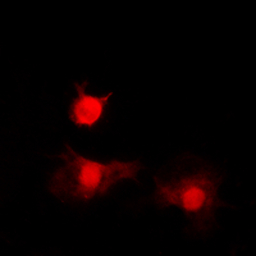

ICC/IF analysis of formalin-fixed A549 cells using GTX32364 HDAC8 (phospho Ser39) antibody.

Red : Primary antibody

Blue : DAPI

Permeabilization : 0.1% Triton X-100 in TBS for 5-10 minutes